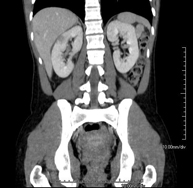

- TC Riñones Prueba diagnóstica que consiste en obtener imágenes bi y tridimensionales del riñón y del sistema urinario de alta definición anatómica mediante el empleo de un equipo de TC (Tomografía Computarizada). Se realiza el estudio antes y después del empleo de contraste yodado en diferentes "fases renales" para una valoración funcional y anatómica (parénquima renal, uréteres, vejiga urinaria, arterias y venas renales, etc.), así como las estructuras adyacentes (vena cava inferior, aorta abdominal, hígado, bazo, etc.). Está especialmente indicado ante la sospecha de lesiones renales, en pacientes con sangre en orina o hematuria, etc. Prueba diagnóstica que consiste en obtener imágenes bi y tridimensionales del riñón y del sistema urinario de alta definición anatómica mediante el empleo de un equipo de TC (Tomografía Computarizada). Se realiza el estudio antes y después del empleo de contraste yodado en diferentes "fases renales" para una valoración funcional y anatómica (parénquima renal, uréteres, vejiga urinaria, arterias y venas renales, etc.), así como las estructuras adyacentes (vena cava inferior, aorta abdominal, hígado, bazo, etc.). Está especialmente indicado ante la sospecha de lesiones renales, en pacientes con sangre en orina o hematuria, etc.

- TC Abdomen Prova diagnòstica que consisteix en obtenir imatges de l'abdomen d'alta definició anatòmica (fetge, vesícula biliar, via biliar, pàncrees, melsa, estómac, intestins, ronyons, estructures vasculars, bufeta, úter i ovaris, etc.) mitjançant l'ús d'un equip de TC (Tomografia Computeritzada). Aquestes imatges s'estudien posteriorment en una estació de treball que permet reconstruccions bidimensional en diferents plans de l'espai, i també reconstruccions tridimensionals (3D: volumètriques). La majoria d'estudis requereixen l'ús de contrast iodat per millorar la definició de les imatges. Prova diagnòstica que consisteix en obtenir imatges de l'abdomen d'alta definició anatòmica (fetge, vesícula biliar, via biliar, pàncrees, melsa, estómac, intestins, ronyons, estructures vasculars, bufeta, úter i ovaris, etc.) mitjançant l'ús d'un equip de TC (Tomografia Computeritzada). Aquestes imatges s'estudien posteriorment en una estació de treball que permet reconstruccions bidimensional en diferents plans de l'espai, i també reconstruccions tridimensionals (3D: volumètriques). La majoria d'estudis requereixen l'ús de contrast iodat per millorar la definició de les imatges.